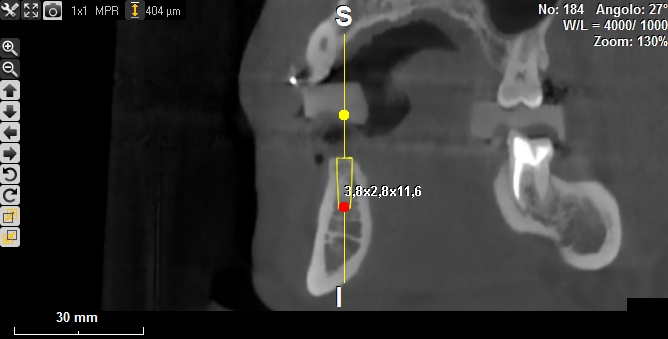

Progettazione virtuale / chirurgia guidata Un esempio della progettazione 3D di un intervento di posizionamento implantare SENZA BISTURI. Photogallery: